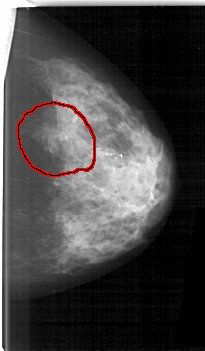

D_4114_1.LEFT_CC

LEFT_CC LINES 5251 PIXELS_PER_LINE 3061 BITS_PER_PIXEL 12 RESOLUTION 43.5 OVERLAY

FILE: D_4114_1.LEFT_CC.OVERLAY

TOTAL_ABNORMALITIES 1

ABNORMALITY 1

LESION_TYPE MASS SHAPE IRREGULAR MARGINS ILL_DEFINED

ASSESSMENT 3

SUBTLETY 4

PATHOLOGY MALIGNANT

TOTAL_OUTLINES 1

BOUNDARY